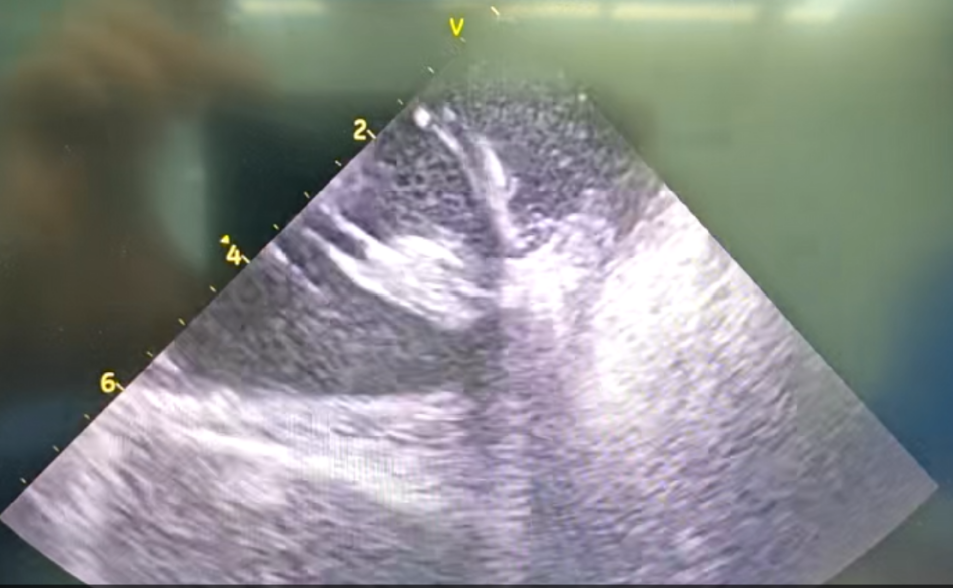

心外膜基质

部分内膜室速靶点电位

王林林主任医师谨慎操作,成功进入心外膜达到病变位置。术中,患者反复自发多形态室速,且转为室扑,同时出现血流动力学不稳定,需多次电除颤方能终止发作,标测难度极大。这就要求医疗团队必须在有限的标测时间内精准定位室速消融靶点,并结合心内外膜基质特征制定消融策略。经针对性消融后,患者未再自发室速,且室性早搏转为单一形态,经判定为右心室乳头肌来源,随即予以一并消融。术后经心室程序电刺激验证,室速未再被诱发。